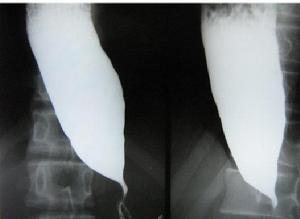

X線鋇劑造影症狀可在術後數日至數年出現,表現為中上腹持續性或無規律性燒灼痛,進食後稍加重,服抗酸劑無效。15%~25%噯出膽汁或有膽汁性嘔吐,嘔吐後症狀無明顯緩解,嘔吐常於早晨清醒時發生。X線鋇劑造影檢查不能確定診斷。由於胃黏膜糜爛引起失血,可致術後低色素性貧血。

膽汁手術後反流性胃炎應與輸入袢綜合徵鑑別,後者是因輸入袢近吻合口處的間歇性梗阻造成,二者有相似之處,但治療不同。輸入袢綜合徵表現為進食後即感陣發性上腹痛、腹脹,常有膽汁性嘔吐,但嘔吐後症狀即緩解,由於食物在嘔吐前已進入輸出袢,故嘔吐物中無食物。X線鋇劑造影檢查可確定診斷。